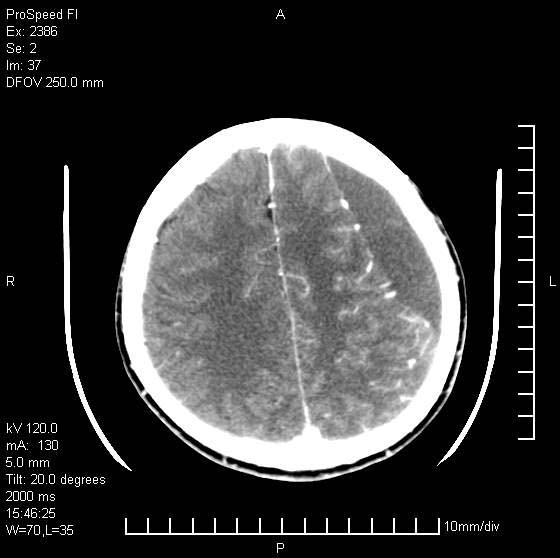

以下是引用天南地北在2007-9-19 18:43:00的发言:[br]典型慢性硬膜外血肿[br][br][本贴已被 天南地北 于 2007-9-19 18:44:11 修改过]

以下是引用曼一拍在2007-9-20 11:06:00的发言:[br]支持慢性硬膜下血肿.[br]慢性硬膜下积液:血肿有包膜,ct值稍高于脑脊液,增强可有染色。不典型者血肿可多呈梭形.是硬脑膜与蛛网膜之间的潜在腔隙内的血肿。[br]鉴别:[br]1\\硬膜外血肿:是颅脑外伤后脑膜或板障内血管破裂,血液在颅骨与硬膜之间积聚所致.通常是脑膜动脉破裂,也可因静脉窦破裂或颅骨的板障静脉出血,发生于外伤的着力部,常与颅骨骨折并存。脑膜动脉出血则急,若是板障静脉出血在则可有慢性。[br]2\\硬膜下积液:(硬膜下水瘤)[br]是由于蛛网膜破裂,脑脊液经蛛网膜破口进入硬膜下腔不能回流。或水肿阻塞而形成。[br]ct表现:颅骨内板下方新月形低密度区近似脑脊液密度;占位效应清,周围无脑水肿。[br]